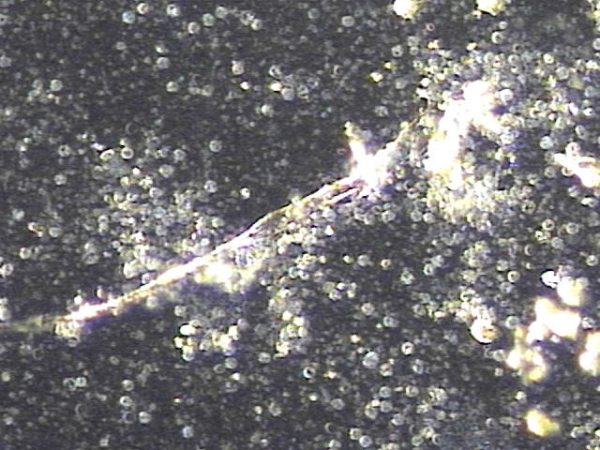

주 2회 전립선과 사정관, 정낭 그리고 정관등의 표적 치료후 치료된 혈정액등의 현미경학적 자료 입니다.

This microscopic image demonstrates that blood components previously present in the semen have improved following twice-weekly targeted treatment of the prostate, ejaculatory ducts, seminal vesicles, and vas deferens.

주 2회 전립선과 정낭 그리고 정관등의 표적 치료후 탈락된 상피세포와 혈정액 그리고 염증덩어리가 치료되고 있는 현미경학적 자료입니다.

This microscopic image demonstrates that previously accumulated shed epithelial cells, blood in the semen, and inflammatory material are resolving after targeted treatment of the prostate, seminal vesicles, and vas deferens performed twice a week.

횟수를 더할수록 혈정액과 염증덩어리가 감소하고 탈락되어 막혀 있던 상피세포가 치료되고 있는 현미경학적 자료입니다.

As the number of treatment sessions increases, this microscopic image demonstrates that blood in the semen and inflammatory material are steadily reducing, while the previously blocked ducts caused by shed epithelial cells are improving and reopening.